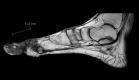

The aim of this study was to review the available literature concerning Madura foot ("mycetoma") caused by Madurella mycetomatis in immunocompromised patients. With a systematic literature search, we identified only three papers, describing a total of three immunocompromised patients. Hence, the clinical presentation and prognosis of the disease in this patient population have not yet been well described. In addition, we present a case from our institution, illustrating the complexity of the treatment of this rare disease. Although very rare in non-endemic countries, we emphasize that mycetoma should be included in the differential diagnoses of (immunocompromised) patients who have been residing in a geographical area where the disease is endemic and presenting with soft tissue inflammation of one of the extremities.